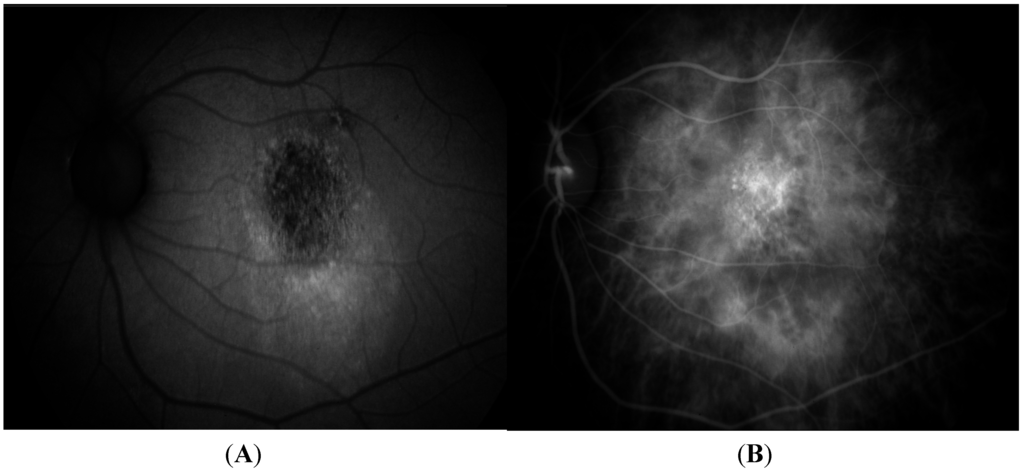

7. Fundus Autofluorescence

- Yamagishi, T.; Koizumi, H.; Yamazaki, T.; Kinoshita, S. Fundus autofluorescence in polypoidal choroidal vasculopathy. Ophthalmology 2012, 119, 1650–1657. [Google Scholar] [CrossRef] [PubMed]

- Yamagishi, T.; Koizumi, H.; Yamazaki, T.; Kinoshita, S. Changes in fundus autofluorescence after treatments for polypoidal choroidal vasculopathy. Br. J. Ophthalmol. 2014, 98, 780–784. [Google Scholar] [CrossRef] [PubMed]